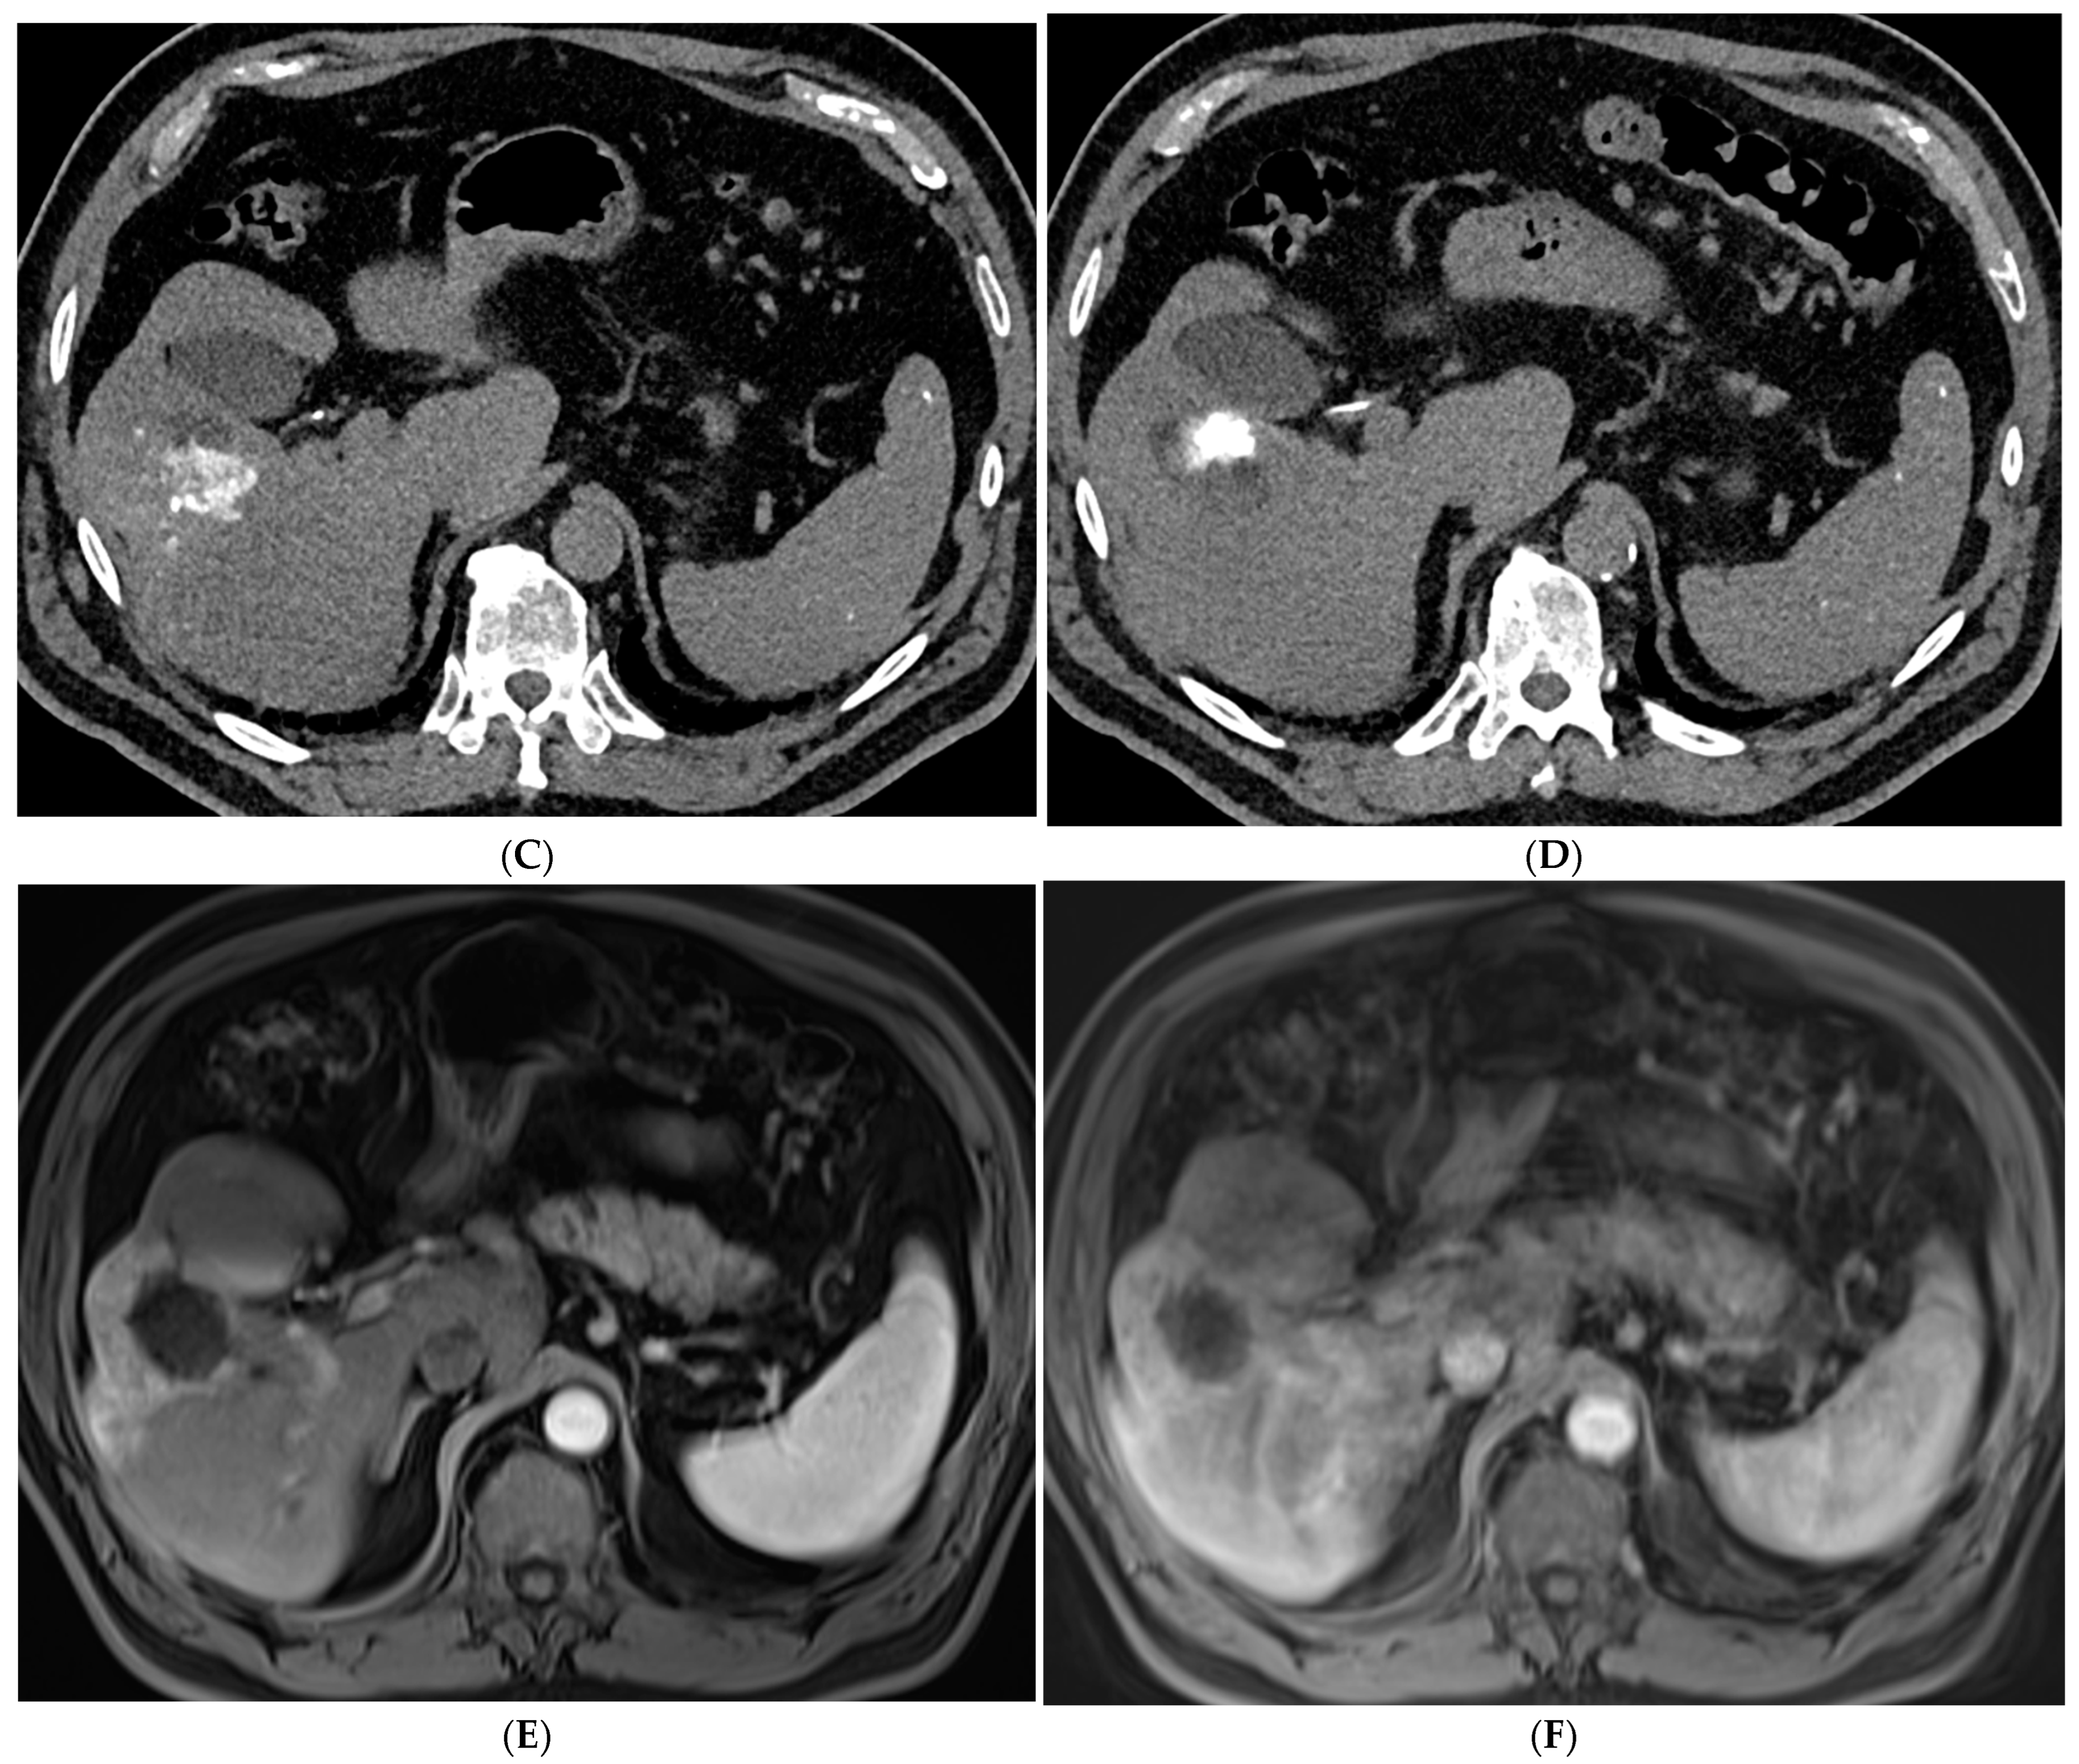

TACE is the mainstay of treatment in intermediate stage (BCLC-B) HCC. Conventional TACE (cTACE) is performed with a combination of ethiodized oil and chemotherapy, in the US most commonly doxorubicin, either alone or in combination with mitomycin and cisplatin, followed by an embolic agent such as polyvinyl alcohol (PVA) or a gelatin sponge (Figure 2). TACE with drug-eluting beads (DEB-TACE) uses doxorubicin-loaded microspheres as a simultaneous drug-delivery and embolic agent. In the PRECISION V trial, the two techniques were compared, and results demonstrated a decrease in systemic side effects with DEB-TACE with similar survival rates [27]. Another study by Li et al. similarly showed a decrease in complications and prolonged interval between treatments with DEB-TACE [28]. In a more recent study, the PRESIDENT trial, cTACE was again compared to the more modern techniques of DEB-TACE [29]. The results demonstrated that the cTACE cohort had higher rates of complete response at 1- and 3-month time points (84.2%, 75.2%) versus the DEB-TACE group (35.7%, 27.6%). However, the cTACE group had significantly higher rates of adverse events attributed to post embolization syndrome including fever, fatigue, malaise, abdominal pain, anorexia, and lab abnormalities including elevated bilirubin, AST, ALT, and hypoalbuminemia [29].

Figure 2.

88-year-old woman with HCC on a background of cirrhosis secondary to autoimmune hepatitis treated with conventional TACE. (A) Arterial phase MRI showing a 2.2 cm arterially enhancing lesion in hepatic segment 8. (B) Delayed phase MRI showing washout of the lesion. (C) Intraprocedural CTA demonstrating supply to the hypervascular lesion from the segment 8 arterial branch. (D) Post procedure non-contrast CT demonstrating the ethiodized oil deposition within the tumor and surrounding segment 8 parenchyma. (E) Follow up arterial phase MRI one month after treatment demonstrating no arterial enhancement within the treated lesion consistent with complete response.